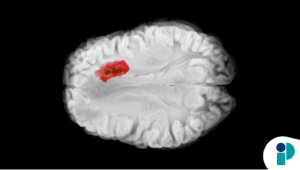

Por otro lado, se están realizando investigaciones innovadoras que podrían cambiar el paradigma de la detección del cáncer. En el ámbito de la oncología en Puerto Rico, se están preparando ensayos clínicos que permitirán realizar pruebas de sangre en pacientes asintomáticos que se someten a colonoscopías. Esto podría representar un avance significativo en la detección temprana de cáncer de colon.